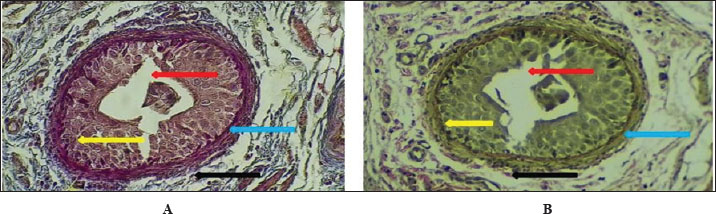

Figure 6 shows that the maturation of kidney tissue was visible on the later low-power H&E section of the 2-week-old hamster kidney compared with the 1-week specimen. The red arrow indicates how the renal cortex parenchyma is arranged, and the tubular regions are increasingly gathered and distinguished. Because the glomerulus was better developed, there was a clearer and bigger outline of the renal corpuscle. The yellow arrow marks the tubules that have been collected, and they now have distinct profiles and clear lines between epithelial cells, showing that urine concentration is starting and nephron structures are also dividing further. Figure 7 (Section Masson) implies that the capsule of the kidney cortex has received more fibrous support than in the previous stages. Columnar epithelial cells (marked by the blue arrow) were longer and better arranged in the inner part of the sac than they had been a week ago. The red or pink epithelial layer and the cytoplasmic structure were clearer from the blue collagen, indicating the formation of different tissue compartments in the body. Figure 8 presents the appearance of a hamster’s ureter at 2 weeks, stained with H&E in Figure A and with Alcian blue in Figure B at both 10x and 20x magnification. The lumen (red arrow) was slender and surrounded by a better-defined epithelial lining in both images. Simple squamous epithelial cells are marked by the yellow arrow in the transitional epithelium, and the blue arrow indicates a smooth muscle layer below. Mucosubstances in the epithelial layer became more noticeable in panel B because the Alcian blue stain was used, suggesting more mucus secretion for passing urine and shielding the bladder wall. Figure 9 includes two histological images of the renal cortex of a 3-week-old hamster. One was stained with hematoxylin and eosin (A) and the other with Masson’s trichrome (B) under 40x magnification. There was an increased formation of renal corpuscles in every area, where the capillary tufts were evident (yellow arrows). The red-marked proximal tubules have a well-formed brush border, and their cytoplasm is colored eosinophilic. Both images have blue arrows that confirm that the renal veins were connected with the blood vessels in the cortex. In Fig. 10, Panels A and B, Masson’s Trichrome (A) and Van Gieson (B) stains were used for transverse sections seen at 20x. The red arrows show where the unambiguous ureteral lumen was located. Simple squamous epithelium was highlighted by yellow arrows and stratified. The blue arrows denote the muscles found in the area, whereas the black arrow in panel B marks the pink layer seen on the outside called the serosa. Currently, the ureter looks complete, as confirmed by its multilayered structure, and is ready. Fig. 11 shows the renal cortex from a 2-month-old hamster stained with PAS (A, 20x) and H&E (B, 40x). Panel A shows that the renal capsule is organized and composed of fibrous tissue. The yellow arrow indicates that the advanced renal corpuscle has a distinct Bowman’s space, and the blue arrow indicates a major proximal tubule marked by its brush border and PAS-positive basement membrane. The black arrow indicates the wider lumen and the pale cytoplasm of the distal tubule. In the H&E image, the two main kinds of tubules were easily identified, proving that the nephron has developed completely and matured in the cortex. At a magnification of 40x, the renal corpuscle is clearly seen in Masson’s Trichrome (A) and Van Gieson (B) stained slides, as shown in Fig. 12. The blue arrows show complete glomerular capillaries that were properly perfused and assigned a consolidated mesangial matrix. These arrows were aimed at the juxtaglomerular cells on the vascular side, indicating that they were ready to release renin. The red arrows show the urinary pole and the proximal tubule entrance, indicating that the nephron was intact. The black arrows indicate sections of the tubules that lie far from the glomerulus. They also highlight how the nephron is made up of important sections and how the corpuscle becomes an effective filtration unit. Fig. 13 shows a sliced ureter in a 2-month-old hamster demonstrating that its structure was fully mature by Masson’s Trichrome (A) and Van Gieson (B) staining. The red arrows show a wideness to the ureter, proving that the epithelial and muscular layers have healed well. The yellow arrows point to a fully developed urothelium and show simple squamous to cuboidal features according to the ureter location. The thicker and more organized circular muscle groups were observed, where the blue arrows were found inside the walls.

Fig. 12. Cross-histopathological section of renal corpuscle in hamsters (2 months old) consisting of glomerular capillaries (blue arrow) and juxtaglomerular cells with urinary pole distal tubule (A- 40x. masons stain, B- 40x. Van Gieson stain).

Fig. 13. Cross-histological section of the ureter in hamsters aged 2 months showing a deep lumen (red arrow) in the middle, a simple squamous epithelial layer (yellow arrow), and smooth muscle (blue arrow), A- 10x. Masson’s trichrome stain, B- 40x. Van Gieson staining.